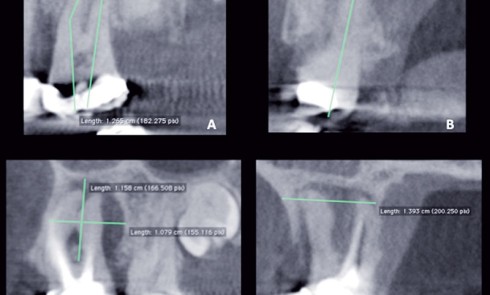

Article réservé à nos abonnés Apport de l’imagerie cone beam en endodontie

L’exploration radiographique du réseau canalaire radiculaire est une nécessité en endodontie. La visualisation de l’endodonte et de son environnement osseux...